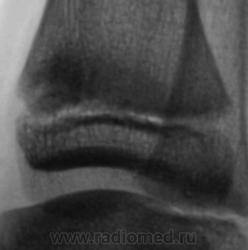

Уважаемый Валентин Львович! А что в жалобах, анамнезе? В переднемедиальной зоне дист. метафиза б/берцовой кости субхондрально под зоной роста участок уплотнения к/структуры, не отграниченный от неизмененной костн. ткани. Возможно, это импрессионный перелом? или остеонекроз? Смущает небольшой очаг аналогичной структуры в таранной кости под медиальным валом блока.

А как же объяснить асимметрию рентгеновской суставной щели?

А на мой взгляд, суставная щель вполне симметрична.

А, что, это за фрагментик?

Алё, детские рентгенологи! Уплотнение костной структуры над зоной роста патологическое или нет?